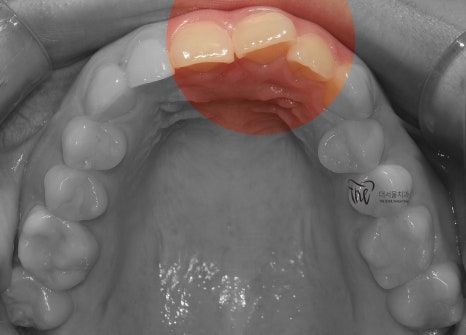

구강 내 사진을 먼저 보여드리면, 윗니가

아랫니를 깊게 물고 있어서 아랫니가 거의

눈에 띄지 않는 것을 보실 수 있습니다.

딱, 전형적 과개교합 의 양상을 보여주고 있습니다.

그러면서 치아의 중심선이 맞지 않으면서

악궁의 크기 또한 비대칭인것을 볼 수 있네요.